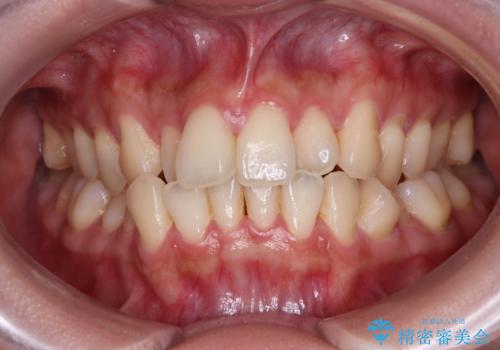

受け口と八重歯を改善 インビザライン矯正治療